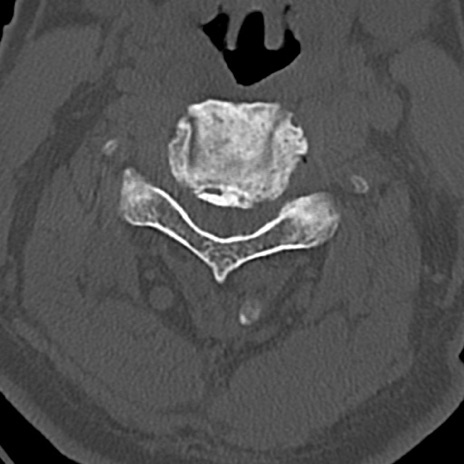

頚椎CT

横断像